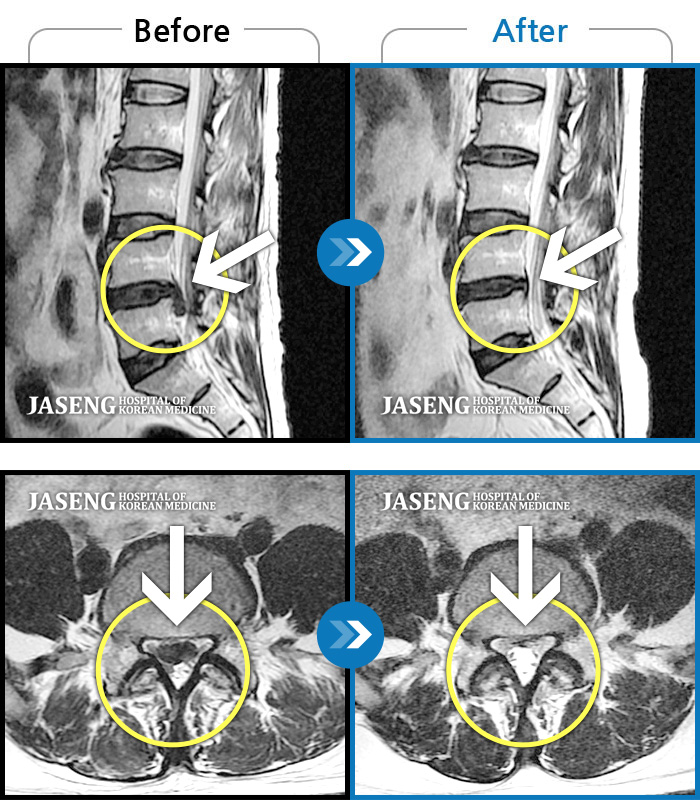

25년 1월 허리통증이 시작되고 잠을 잘수도없고 걸을 수 없을만큼의 상태가 되었을때 다시 김태용 원장님께 진료를 받고 예전 허리수술의(4번5번)(3번4번)디스크탈출증 재발과 협착증의 진단을 받고 지금까지 기나긴 여정의 입원 치료를 하며 곧 퇴원을 앞두고 있습니다.